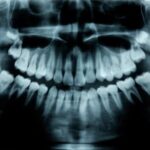

Círculo Odontológico Regional Venado Tuerto

Profesionales en odontología para tu salud bucal

Odontología de vanguardia para la prevención

y tratamiento de enfermedades dentales.